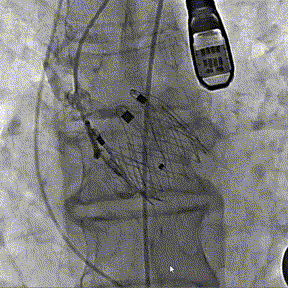

术前DSA造影

瓣膜释放过程

术后DSA影像图

25mm球囊术前进行

瓣膜植入后25mm球囊进行后扩